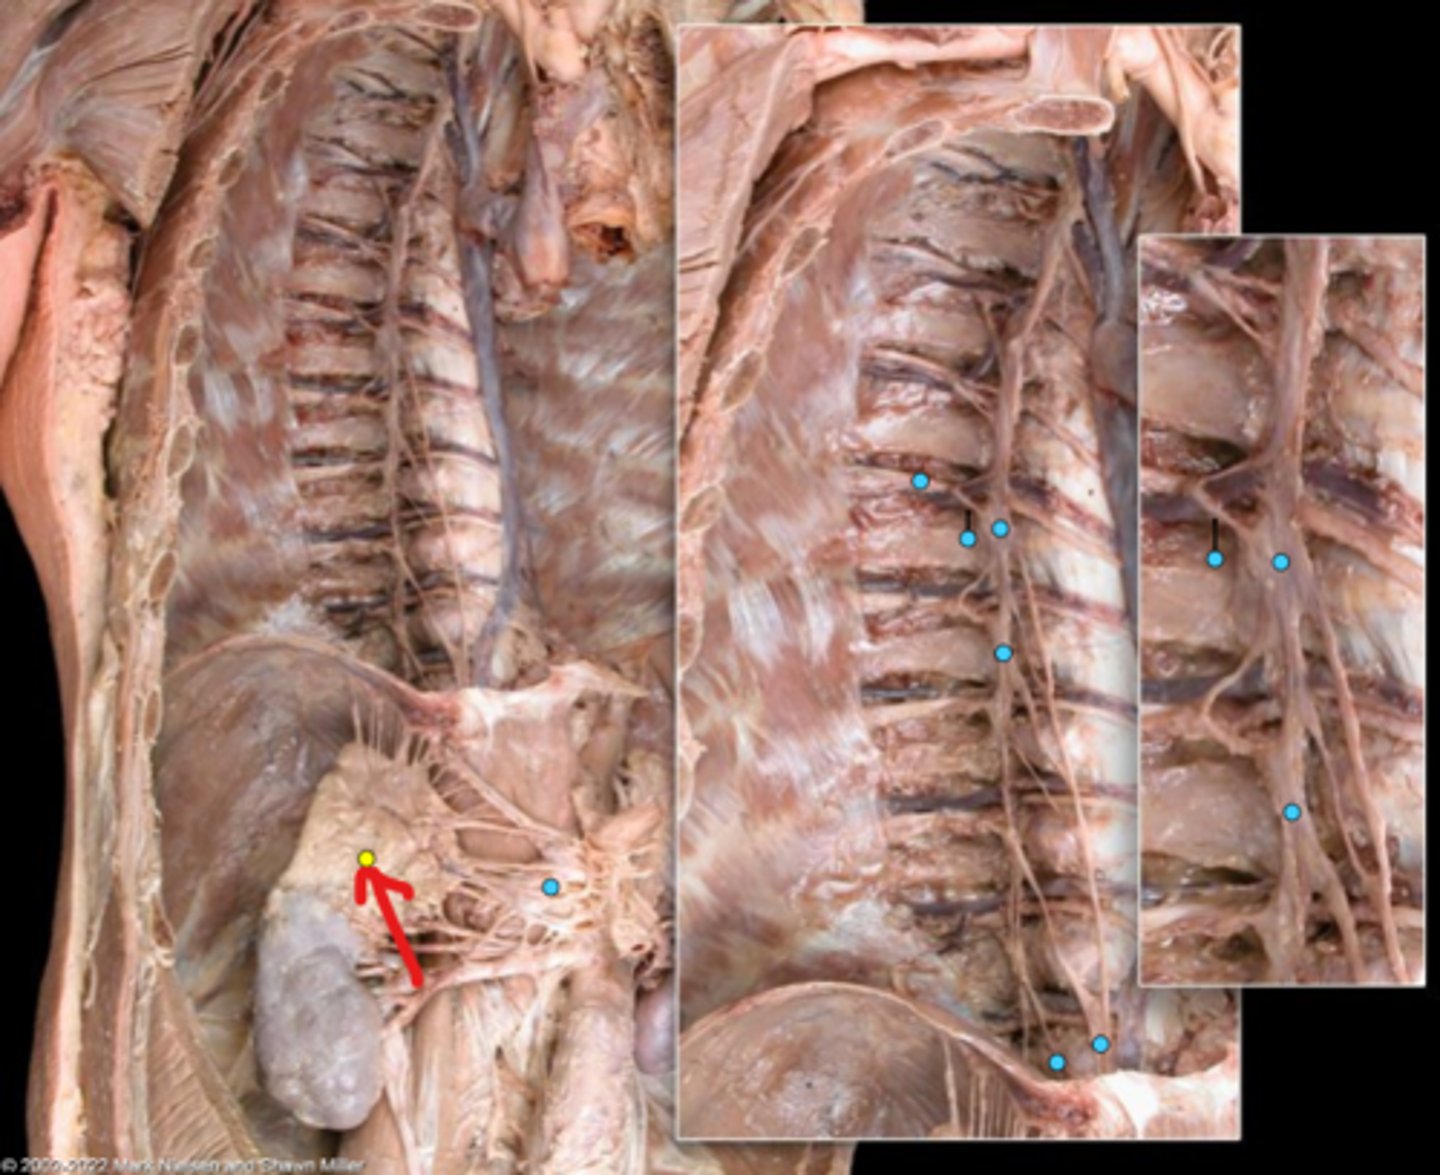

Suprarenal gland

Celiac ganglion

Intercostal nerve

Communicating ramus

Sympathetic trunk ganglion

Sympathetic trunk

Lesser splanchnic nerves

Greater splanchnic nerve

Anterior (ventral) ramus

Spinal nerve trunk

Posterior (dorsal) ramus

Spinal ganglion